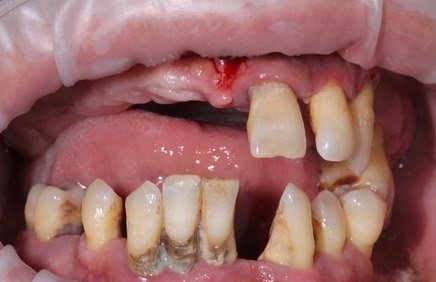

Временные конструкции пациента с генерализованный пародонтитом с применением методики All-on-4 (все на 4-х)

Врач @motordantist